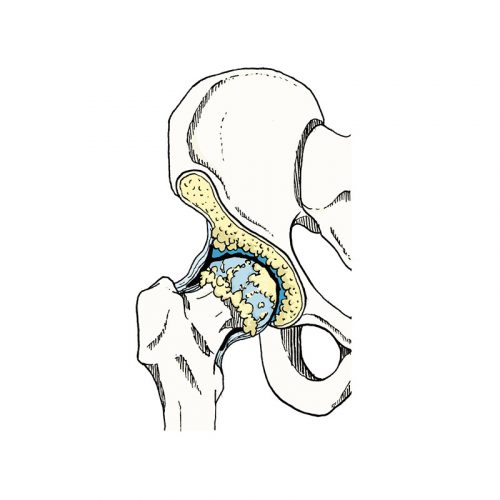

O mundo da ortopedia prepara-se para mais uma edição do 3.º HIP G.I.N. (Global Issue Network) Summit, um evento dedicado às grandes questões da cirurgia da anca. Organizado pelo Lusíadas Knowledge Center em parceria com a UpHill Events, o summit ocorrerá nos dias 21 e 22 de novembro de 2025, na Herdade da Comporta, reunindo…